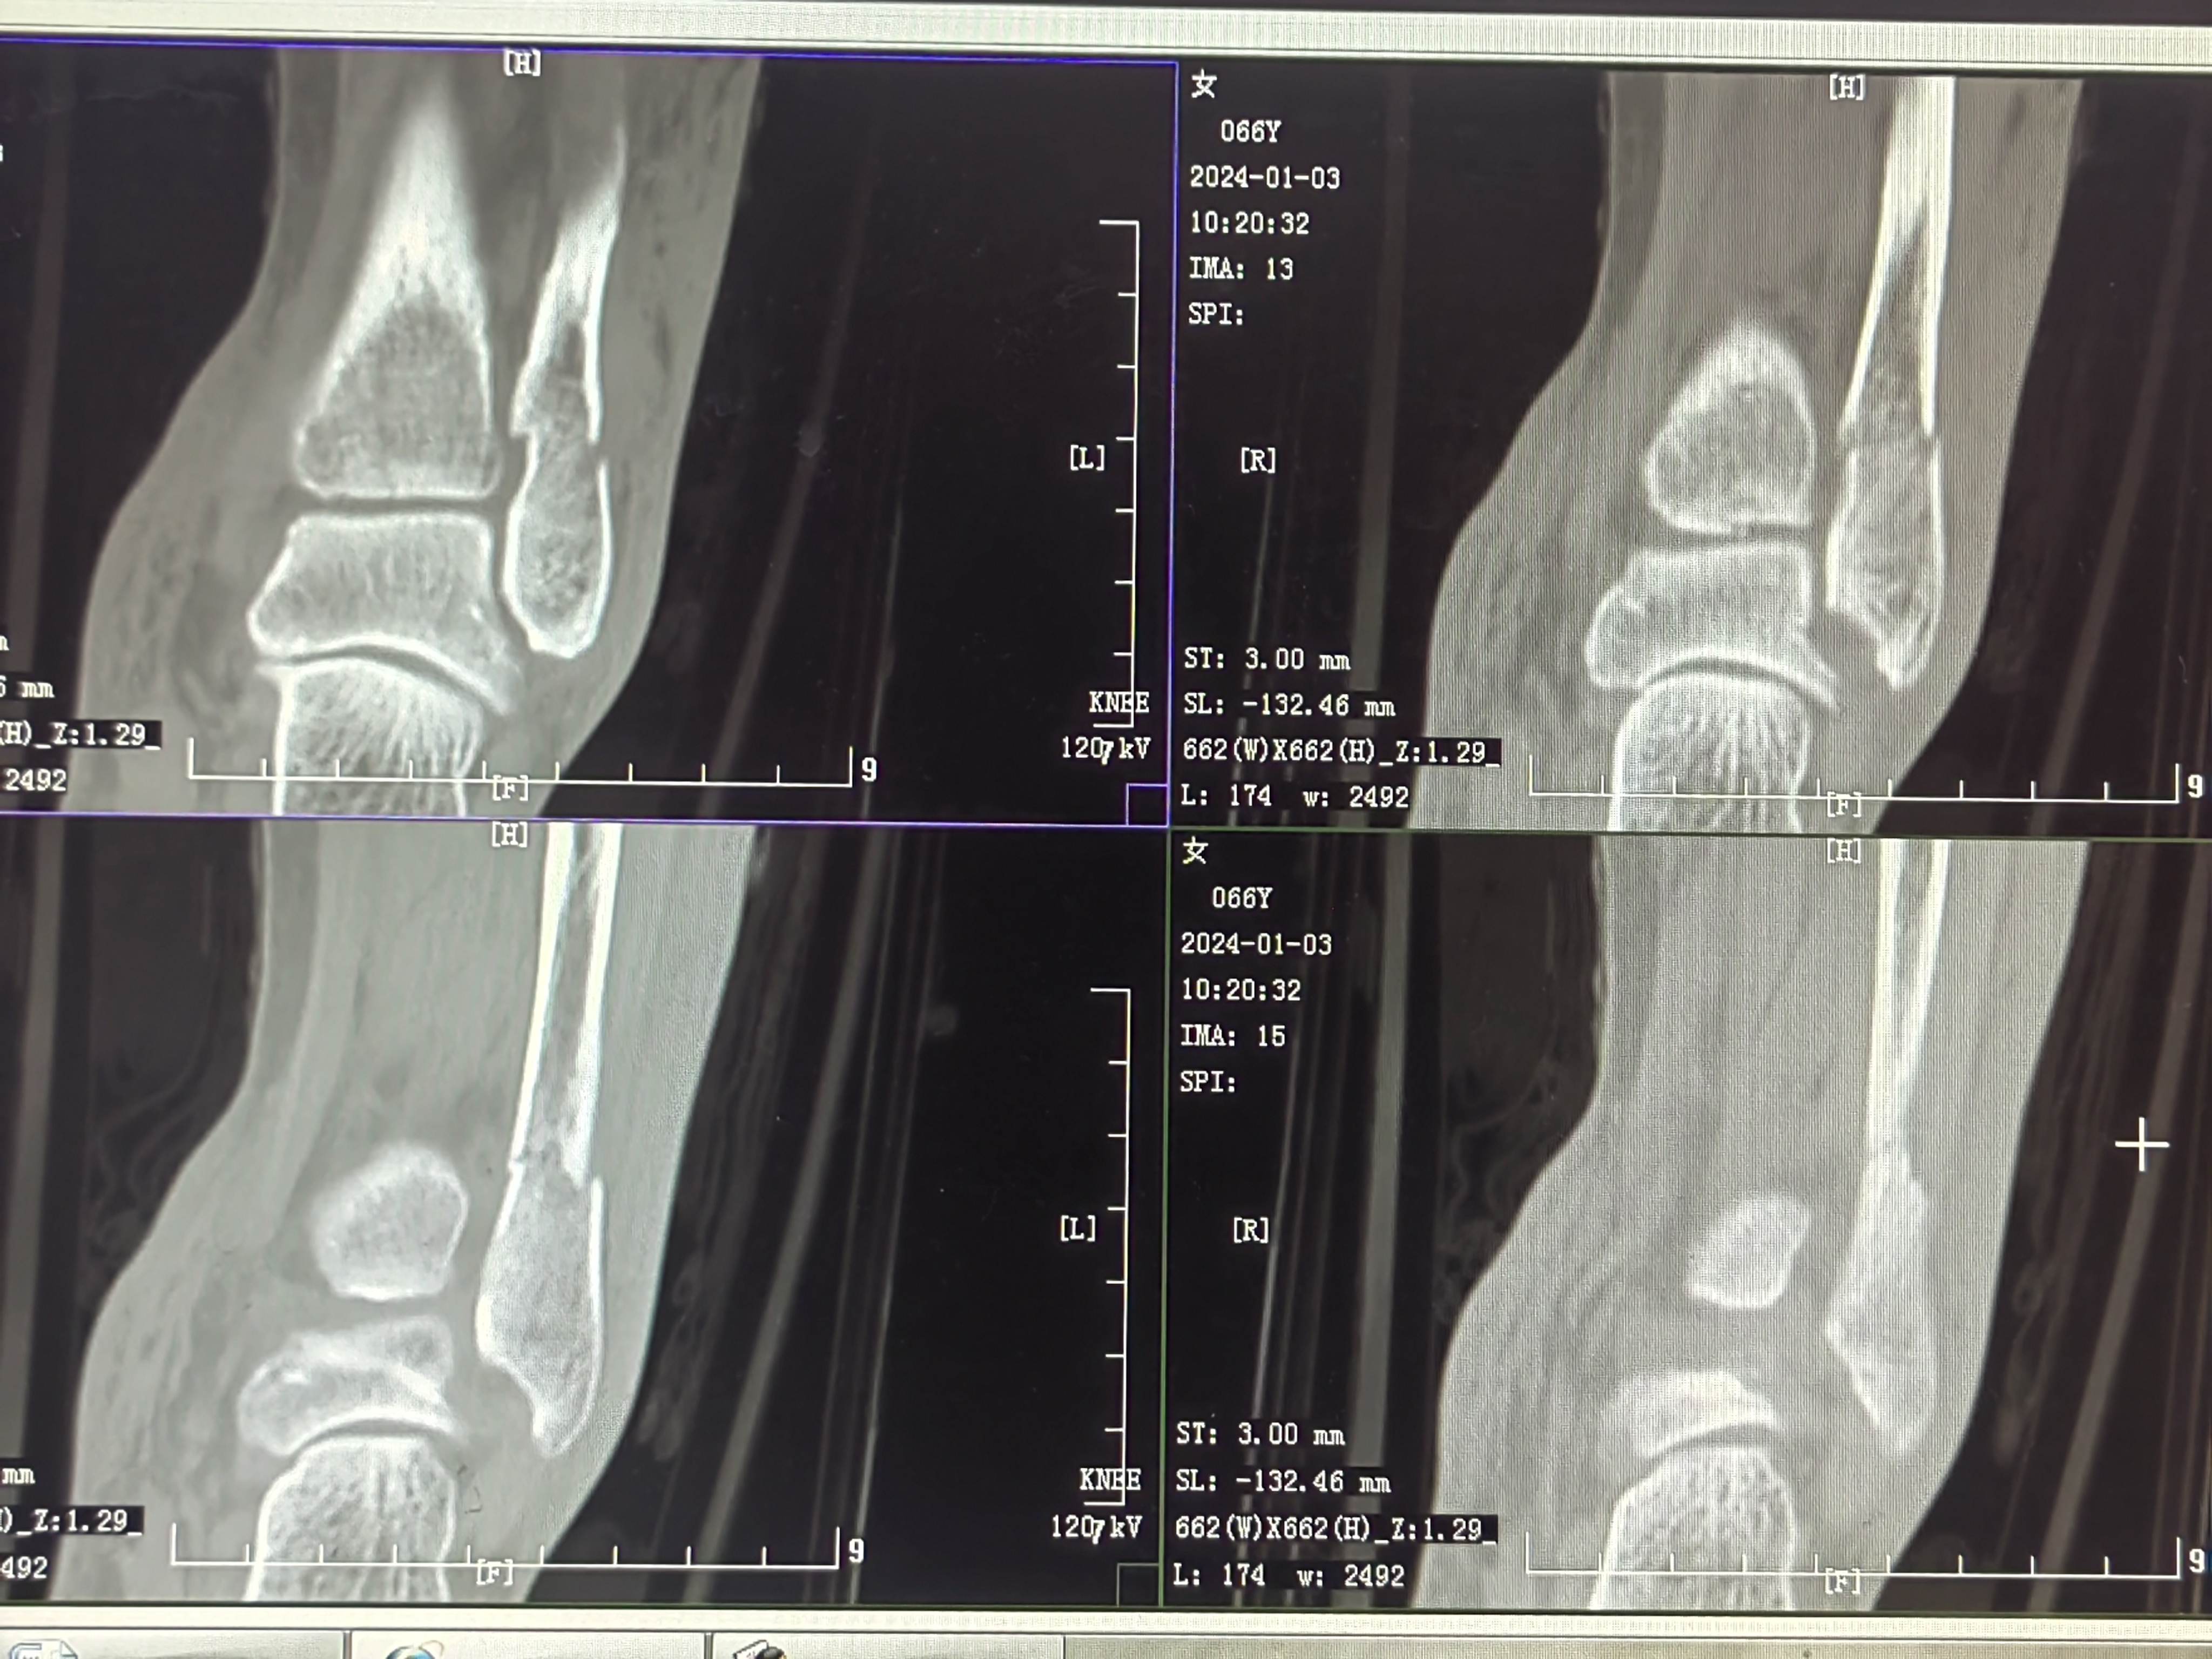

患者矫,女,66岁,左踝扭伤肿痛畸形2小时

初步诊断:左踝关节骨折(L-H分型:旋后外旋型IV)

CT